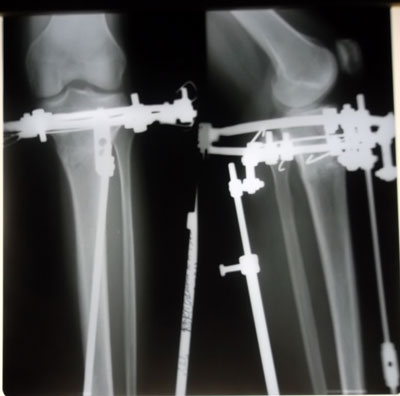

Пациентка Майя.(1978г.р.)

г. Усть - Каменногорск

Дата операции 15.05.2013г.

Дата снятия аппаратов 20.08.2013г.

Срок лечения 94 дня.